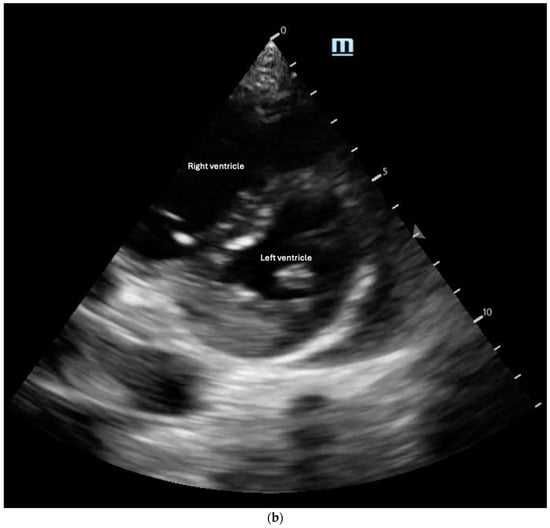

Right ventricular (RV) contractility is essential for maintaining right-sided cardiac output, ensuring blood supply to the pulmonary vasculature and subsequently to the left heart. Unlike the LV, the RV contracts primarily through longitudinal muscle fiber shortening, inward free wall movement, and LV-dependent contraction [32]. As a result, RV contraction occurs predominantly in a longitudinal rather than radial manner. Due to the RV’s greater compliance compared with the LV, its contractility and CO are highly influenced by changes in afterload, which will be discussed in the next section. External pressure changes, such as those seen in cardiac tamponade, can also significantly impact RV function. In tamponade, pericardial fluid compresses the heart chamber, elevating RV diastolic filling pressure and reducing RV output [33]. Owing to the RV’s increased compliance, the RA and the RV are the first chambers to collapse under increased pericardial pressure. Therefore, RA/RV collapse on bedside POCUS in the presence of a pericardial effusion should raise the suspicion of tamponade (Figure 5) [34].

Figure 5.

Anechoic pericardial effusion in apical 4-chamber view.